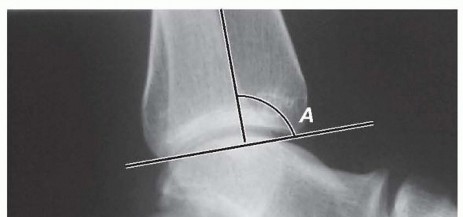

Guided Growth to Correct Limb Deformity DEFINITION The anatomic axis is the mid-diaphyseal line of a bone. Th…